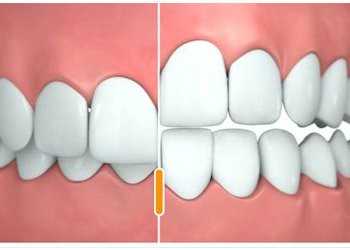

![]()

![Глубокий прикус]()

![глубокий прикус у взрослых]()